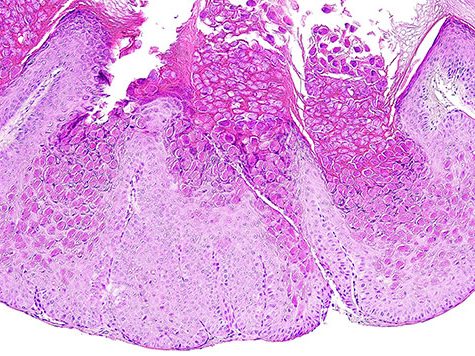

Die meisten Fälle können bereits mit der Standardfärbung Hämatoxylin-Eosin (HE) abschließend befundet werden.

Dies gilt z.B. auch für ein Molluscum contagiosum (s. Foto) mit den charakteristischen viralen Einschlusskörperchen in der verbreiterten Epidermis.